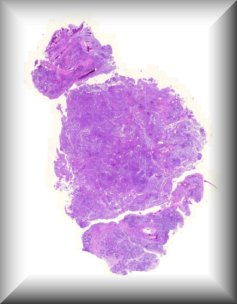

Susan Kennedy: Exenteration specimen of a 70-year-old female who underwent multiple (14) surgeries for conjunctival melanoma over a period of two years. |